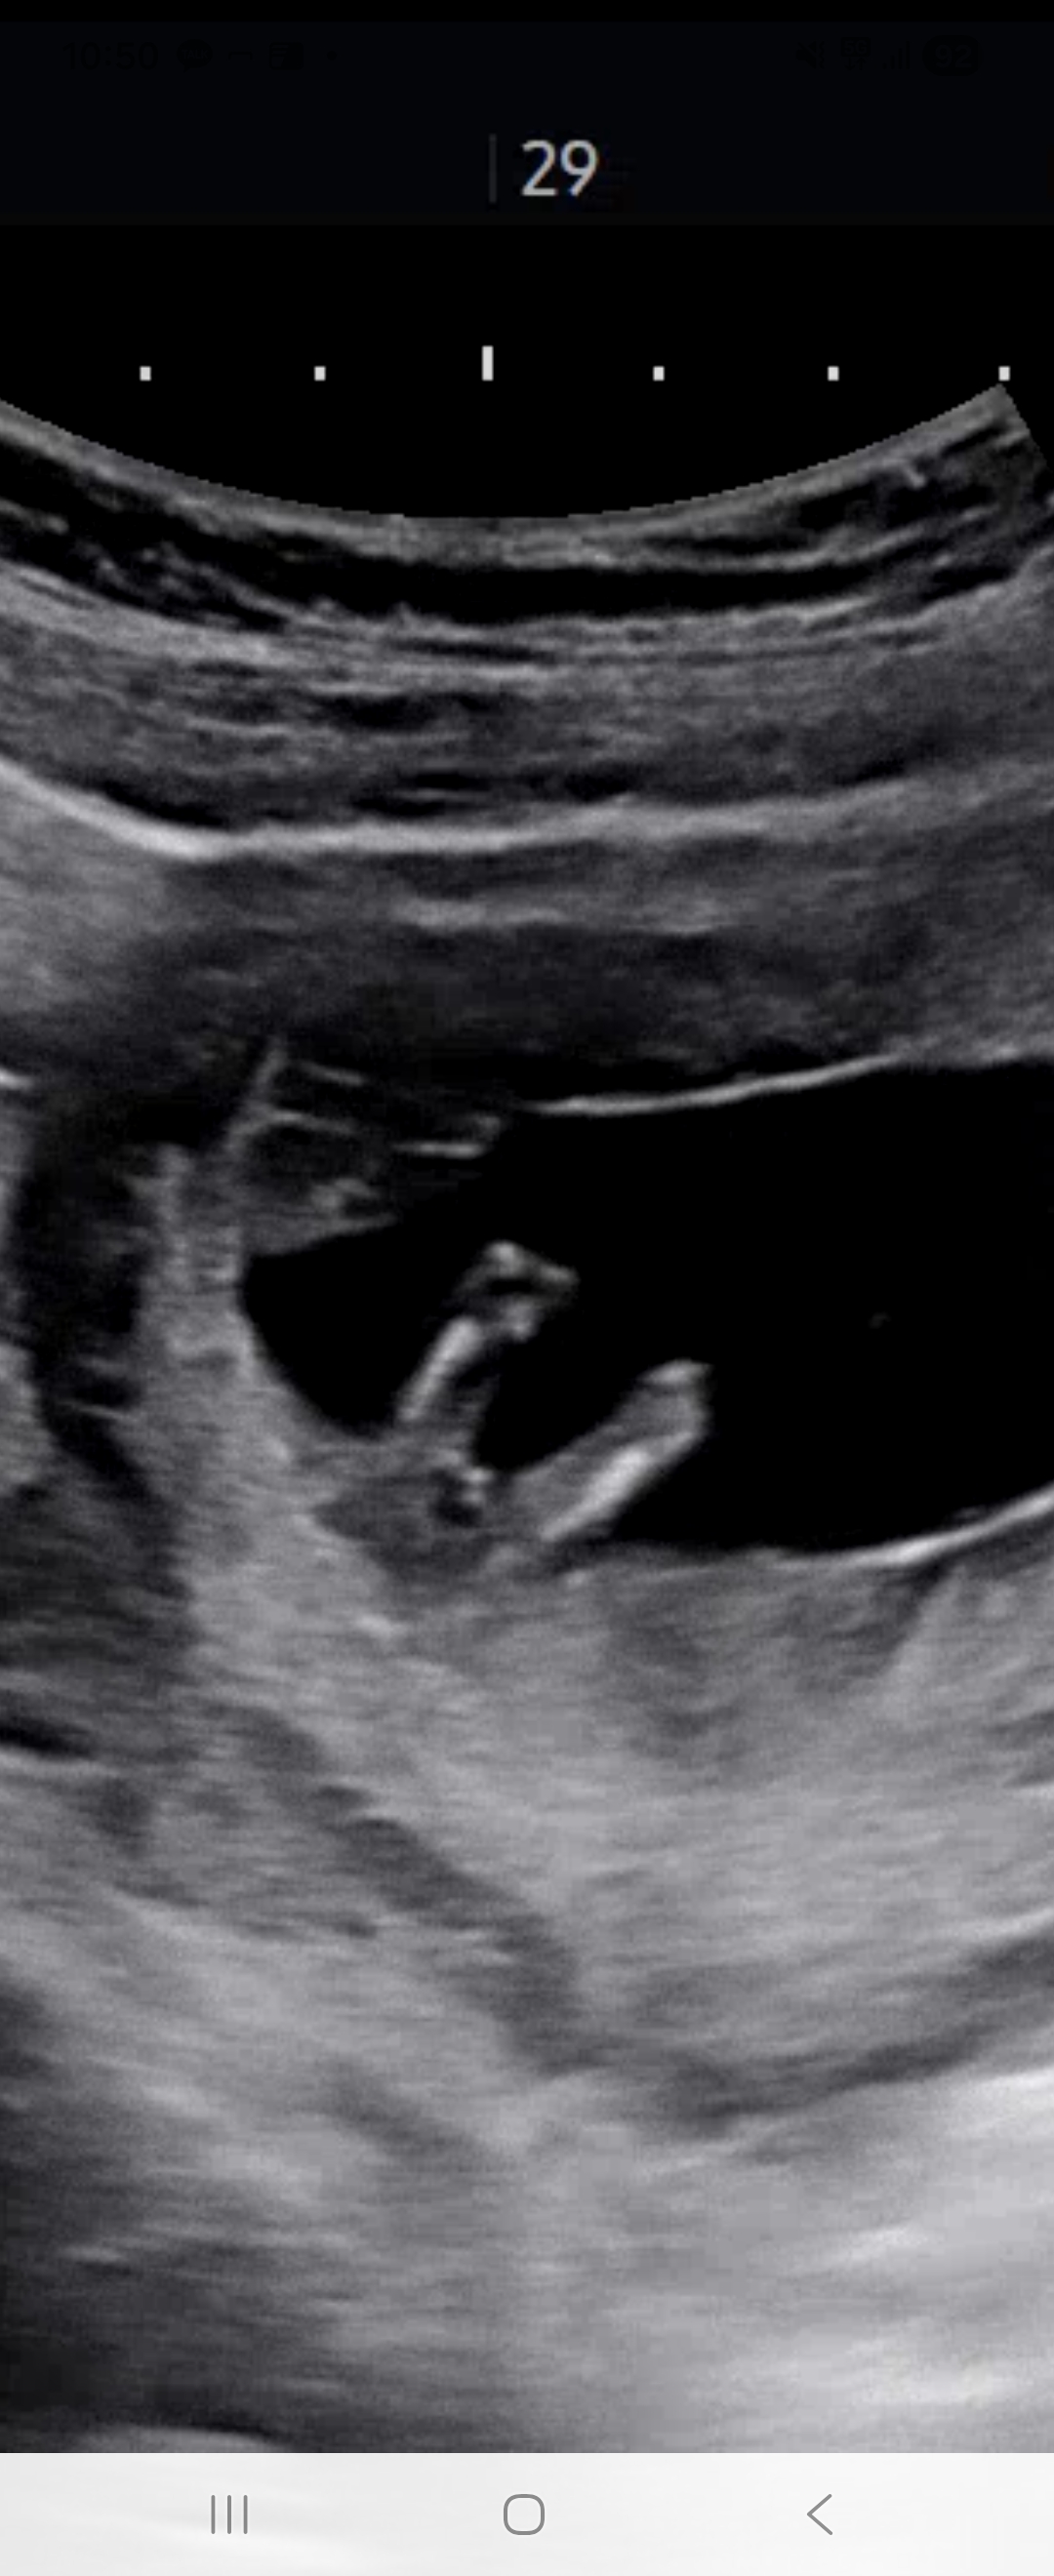

12주4일입니다 매끈한가용??

12주4일이면 딸아들 상관없이 튀어나와 있을줄 알았는데 생각보다 매끈한거보니 딸같기도 하고... 점3개가 신경쓰이기도 하구... 잘 보시는분 계신가용..??